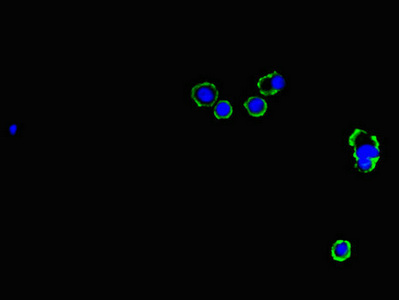

圖片:

應(yīng)用范圍:ELISA, IHC, IF

Application Recommended Dilution IHC 1:20-1:200 IF 1:50-1:200 -